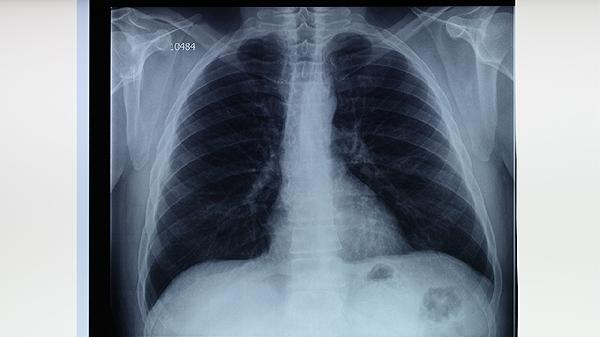

结核菌素试验阳性表明机体曾感染结核分枝杆菌或接种过卡介苗,可能出现局部皮肤硬结。若硬结直径超过特定标准,提示存在结核感染风险。建议进行胸部X线检查排除活动性结核病,必要时使用异烟肼片、利福平胶囊等药物预防性治疗。

若同时出现咳嗽、低热、盗汗等症状,且痰培养检出结核分枝杆菌或胸部影像学显示典型病变,可确诊活动性肺结核。标准治疗方案包含异烟肼片、利福平胶囊、吡嗪酰胺片、乙胺丁醇片等药物联合使用,疗程通常需6-9个月。

肺结核阳性结果需由呼吸科医生综合判断,确诊活动性结核病后应严格遵医嘱完成全程治疗。治疗期间注意营养支持,保证优质蛋白和维生素摄入,避免劳累。密切接触者应进行筛查,居家环境保持通风,患者咳嗽时需遮掩口鼻。定期复查胸部影像学和痰菌检查评估疗效,出现药物不良反应及时就医调整方案。